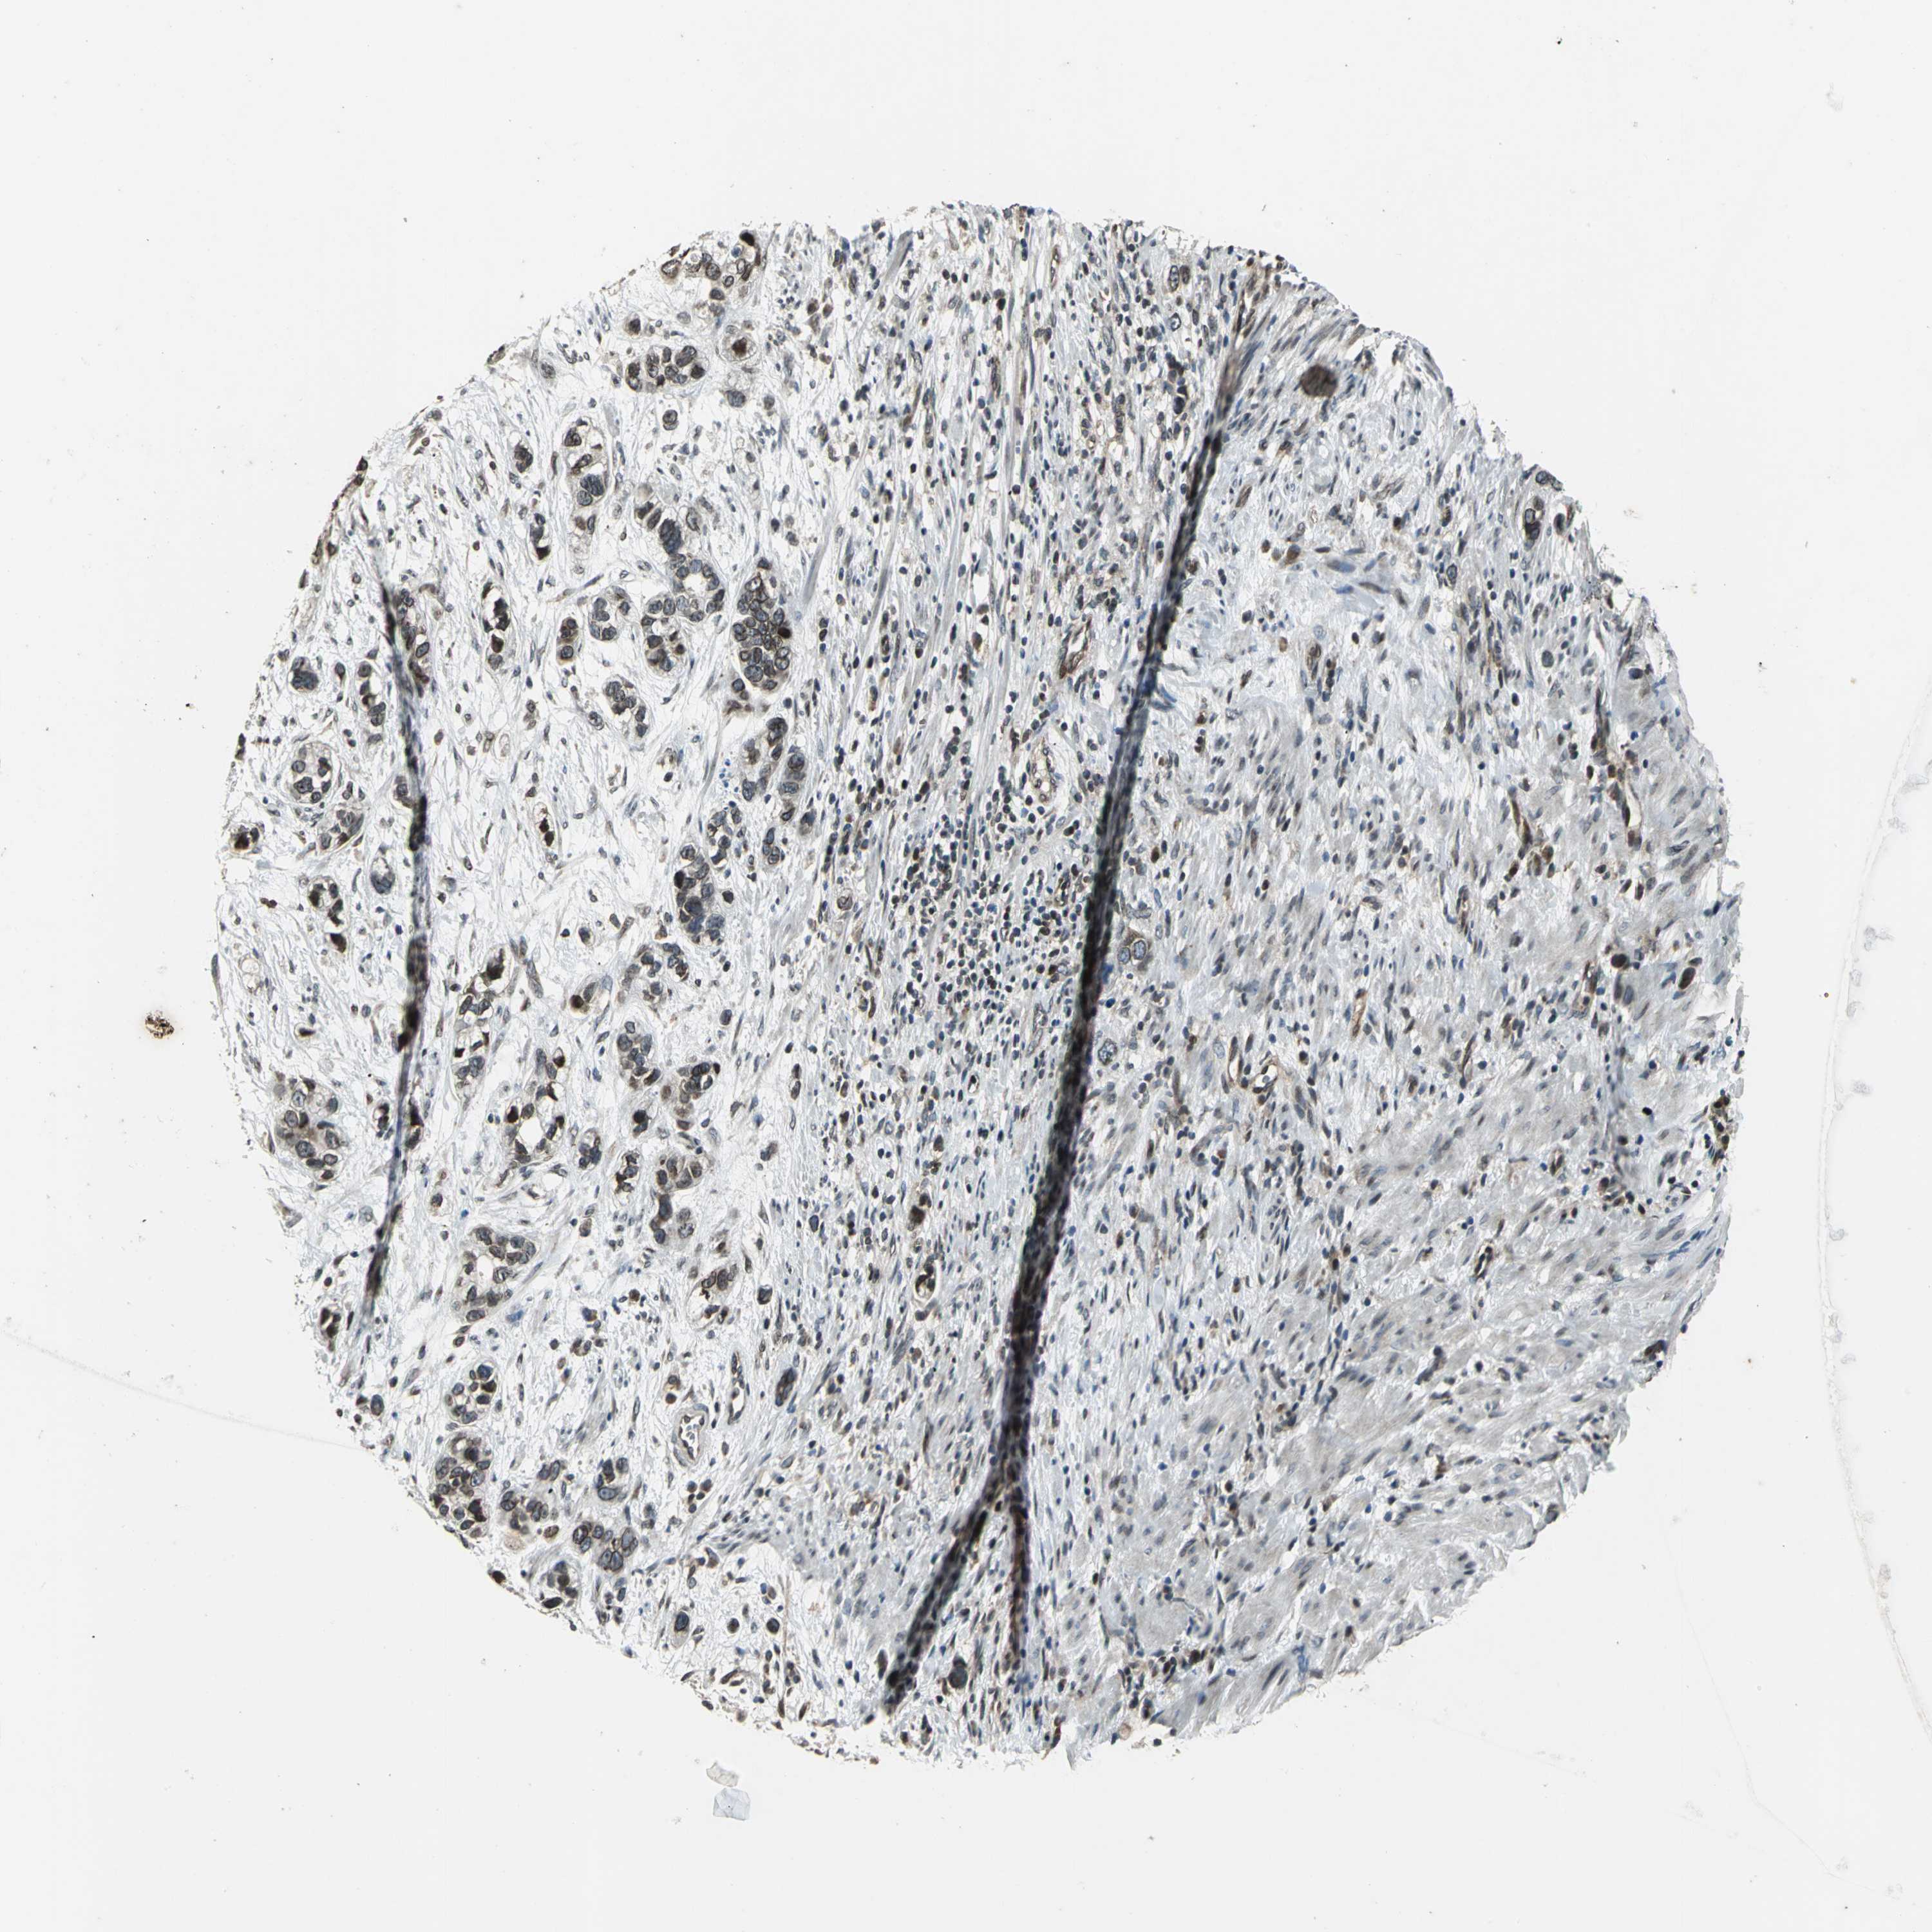

STOMACH CANCER - Protein expressioni

A mouse-over function shows sample information and annotation data. Click on an image to view it in a full screen mode. Samples can be filtered based on level of antibody staining by selecting one or several of the following categories: high, medium, low and not detected. The assay and annotation is described here.

Note that samples used for immunohistochemistry by the Human Protein Atlas do not correspond to samples in the TCGA dataset.

Antibody stainingi

Antibody staining in the annotated cell types in the current human tissue is reported as not detected, low, medium, or high, based on conventional immunohistochemistry profiling in selected tissues. This score is based on the combination of the staining intensity and fraction of stained cells.

Each image is clickable and will lead to virtual microscopy that enables deeper exploration of all samples and also displays staining intensity scores, fraction scores and subcellular localization as well as patient and tissue information for each sample.

Antibody HPA005474

Staining

High

Medium

Low

Not detected

Intensity

Strong

Moderate

Weak

Negative

Quantity

>75%

75%-25%

<25%

None

Location

Nuclear

Cytoplasmic/membranous

Cytoplasmic/membranous,nuclear

Adenocarcinoma, NOS

Adenocarcinoma, High grade